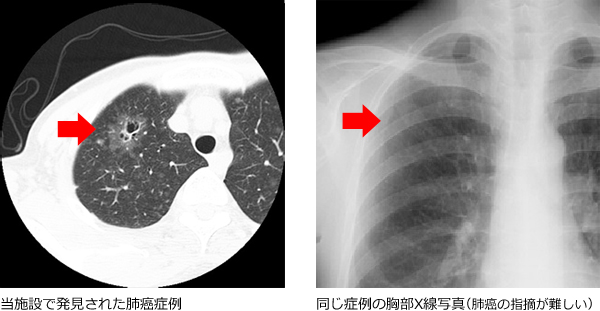

最新のヘリカルCT装置により、胸部の全領域を7mm暑さの横断画像(体の輪切りにした像)で表し、肺がんなどの異常を早期に発見することができます。